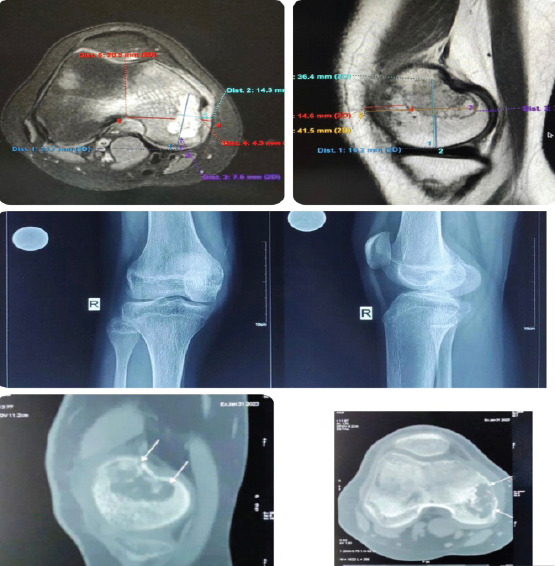

Case report: A 15-year-old female presented with progressive right knee pain of 6 months' duration, worsened by weight-bearing and minimally relieved by analgesics. Clinical examination revealed tenderness and immobile swelling in the region of the medial femoral condyle. Imaging showed characteristic "chicken-wire" calcification, and computed tomography-guided biopsy confirmed chondroblastoma. The patient underwent extended curettage, iliac crest bone grafting, and the use of synthetic bone substitutes. Post-operative rehabilitation showed a good recovery in range of motion and limb function, with no recurrence at follow-up.